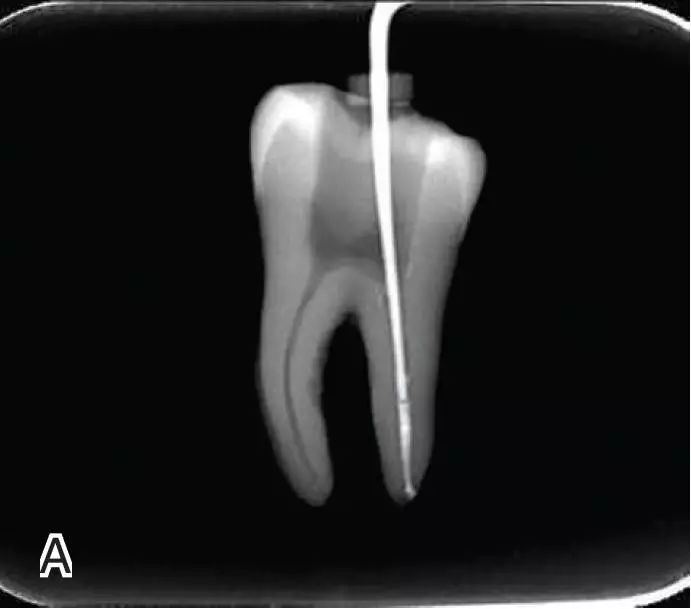

试尖

选择非标准牙胶尖(如0.04、0.06 锥度牙胶尖)作为主尖,型号一般与根管预备最大号的器械型号一致,能到达距根尖0.5~1 mm 处,主尖尖段与根管壁紧密接触。拍试尖X 线片进行确认。